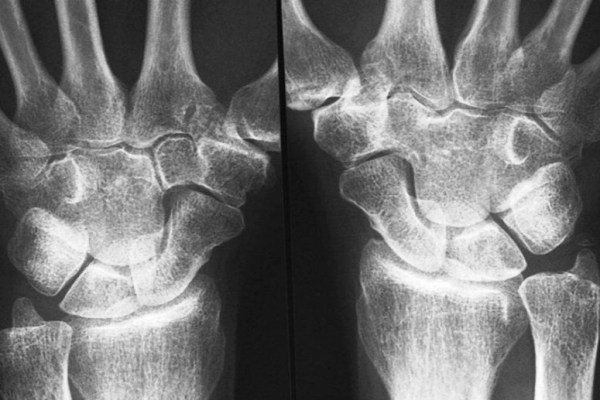

غضروف بافتی مهم در حد فاصل استخوانهاست که امکان حرکت اندامها در جهتهای مختلف را می دهد.

این فناوری پزشکی درحالی ارایه شده که تا پیش از این اکثر تلاشها برای تولید و به کارگیری غضروف مصنوعی ناکام بوده است. علت اصلی این مشکل، فشار قابل توجهی است که به طور طبیعی بر مفاصل وارد می شود و غضروفهای مصنوعی تاب مقاومت در برابر آن را ندارند. اما گویا این نقصان در نوآوری محققان دانشگاه فلوریدا برطرف شده است.

آنها در محیط آزمایشگاهی موفق به تولید بافت غضروفی جدیدی شده اند که تا شش بار مستحکم تر از بهترین نمونه های قبلی است.

ورم مفاصل هم اکنون به عنوان یکی از بیماریهای شایع در دنیا به شمار می آید تا جایی که تنها در آمریکا ۳۰ میلیون نفر با آن دست به گریبان هستند.